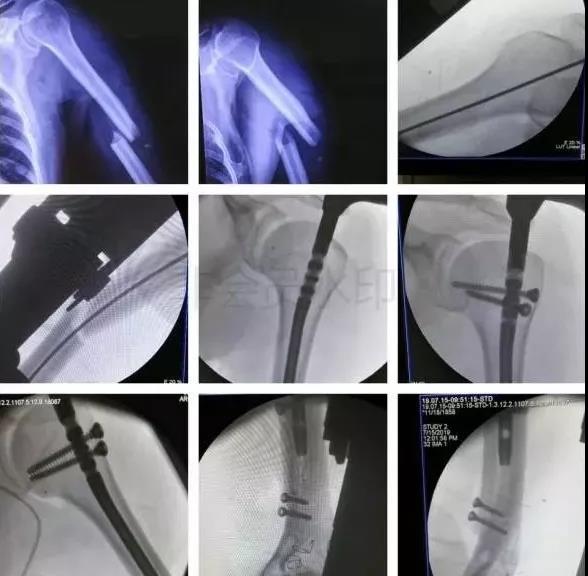

(2)肩胛带骨折

1)锁骨骨折

当骨折块伤及锁骨下动、静脉和臂丛神经时,一致认为是严重的并发症,应立即手术。

1)肱骨近端骨折

脱位伤及腋神经、血管等,或者由于肱二头肌长头腱卡压无法复位,立即手术。

2)肱骨干骨折

- 合并桡神经损伤者,应立即手术。